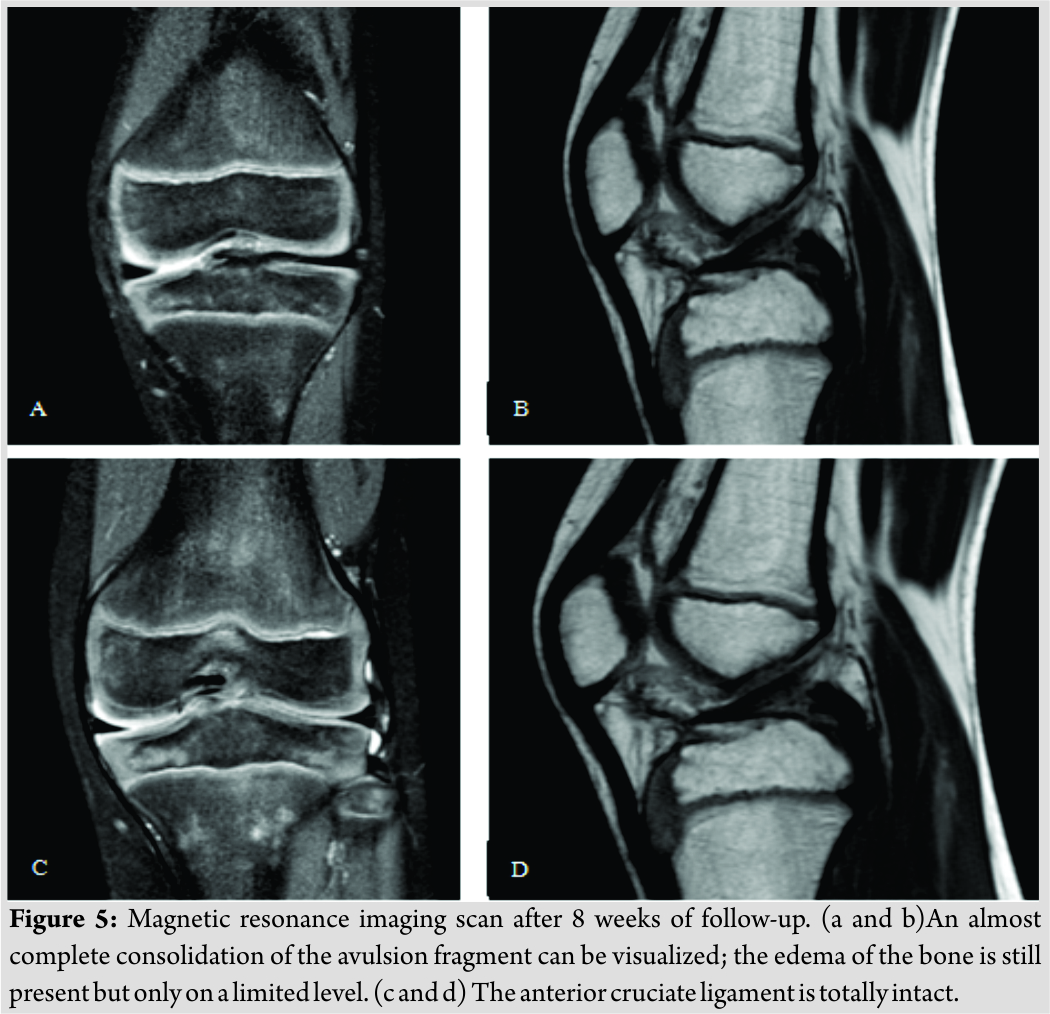

A male Caucasian 8-year-old child presented at the hospital’s emergency department in Belgium. The circumstances of the accident were reported as a fall on the left knee complicated by a contact trauma with another child. At consultation presenting, complaints were a sharp pain in his left knee and difficulties to walk. The pain was scored as 4/10 on the visual analogue scale. In clinical examination, anterior pressure pain, swelling, and a restricted range of motion(flexion up to 100° and extension deficit of 5°) were the main findings. Performing ananterior drawer test and Lachman test, no laxity was documented. On conventional anteroposterior and lateral view of the X-ray, a minimal displaced fracture of the intercondylar eminence, two loose bone fragments, and a bloated suprapatellar bursa indicating hemarthrosis could be evidenced (Fig. 1). A CT scan confirmed a fracture of the intercondylareminence (Fig. 2). The fracture was classified as Meyers and McKeever Type II [4]. The initial treatment provided an adequate pain management with appropriate analgesics and plaster immobilization in 0–5° of flexion. Based on the clinical and radiological findings, a knee arthroscopy was performed 3daysafter injury. The indication for arthroscopic surgery was removal of the intra-articular bony fragments and to evaluate whether the fracture was stable. The fracture of the proximal tibia was visualized through arthroscopy (Fig. 3).

The fracture was classified as Meyers and McKeever Type II [4]. The initial treatment provided an adequate pain management with appropriate analgesics and plaster immobilization in 0–5° of flexion. Based on the clinical and radiological findings, a knee arthroscopy was performed 3daysafter injury. The indication for arthroscopic surgery was removal of the intra-articular bony fragments and to evaluate whether the fracture was stable. The fracture of the proximal tibia was visualized through arthroscopy (Fig. 3).

The ACL was still intact yet showed a discrete laxity. No other fractures or injuries were visualized. Furthermore, the joint was rinsed and the loose bone fragments were removed to improve thee xtension and deep flexion. Peroperatively, the ROM was tested and was complete. Postoperatively, the knee was immobilized in extension with a hard cast. Weight-bearing was not allowed. Physiotherapy was established to strengthen and stabilize the knee. In the first follow-upconsultation 1 week after surgery, a new hard cast was applied for one more week. The patient was instructed to continue the isometric exercises for adequate revalidation. After 2 weeks of cast immobilization, an extension brace was applied for another 2–3 weeks. 6 weeks after the initial trauma, clinical examination showed a positive clinical course. A follow-up CT scan was performed (Fig. 4) that could show a starting consolidation. A CT scan examination was discussed with the family of our patient since his wish was to start sporting (football) early. Furthermore, CT scan is superior to X-ray with the disadvantage of a higher radiation dose. The extension brace was removed and a soft walking brace was applied. The patient was allowed to walk by full weight-bearing, taking pain and stability into account. A T1-weighted magnetic resonance imaging (MRI) scan was performed at 8weeks of follow-up (Fig. 5).This examination was initially performed because of a new trauma and was ordered by the general practitioner. However, it is useful to present the result of the MRI in this case report. The MRI showed an almost complete consolidation alongside very limited edema of the bone (Fig. 5a and b). The ACL and posterior cruciate ligament (PCL)weretotally intact (Fig. 5c and d). Clinically, the knee showed normal stability. The walking brace was permanently removed, and the patient was allowed to perform routine daily activities including all sportive activities. No more follow-up consultations were planned.